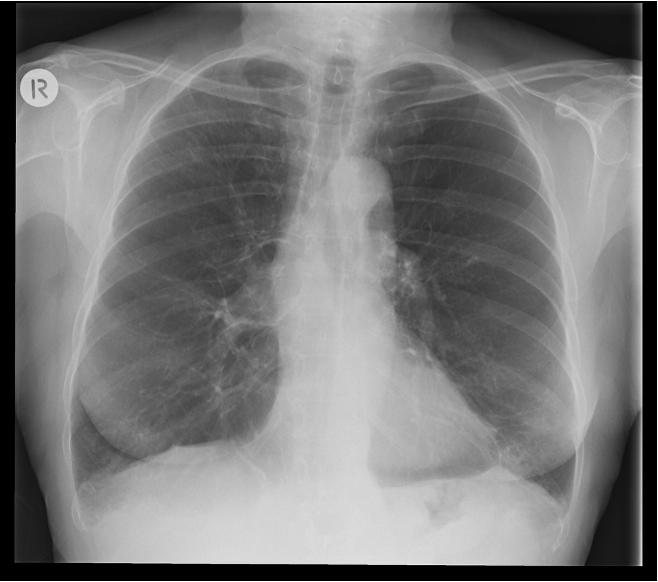

New cards

What does this refer to

CXR in Asthma